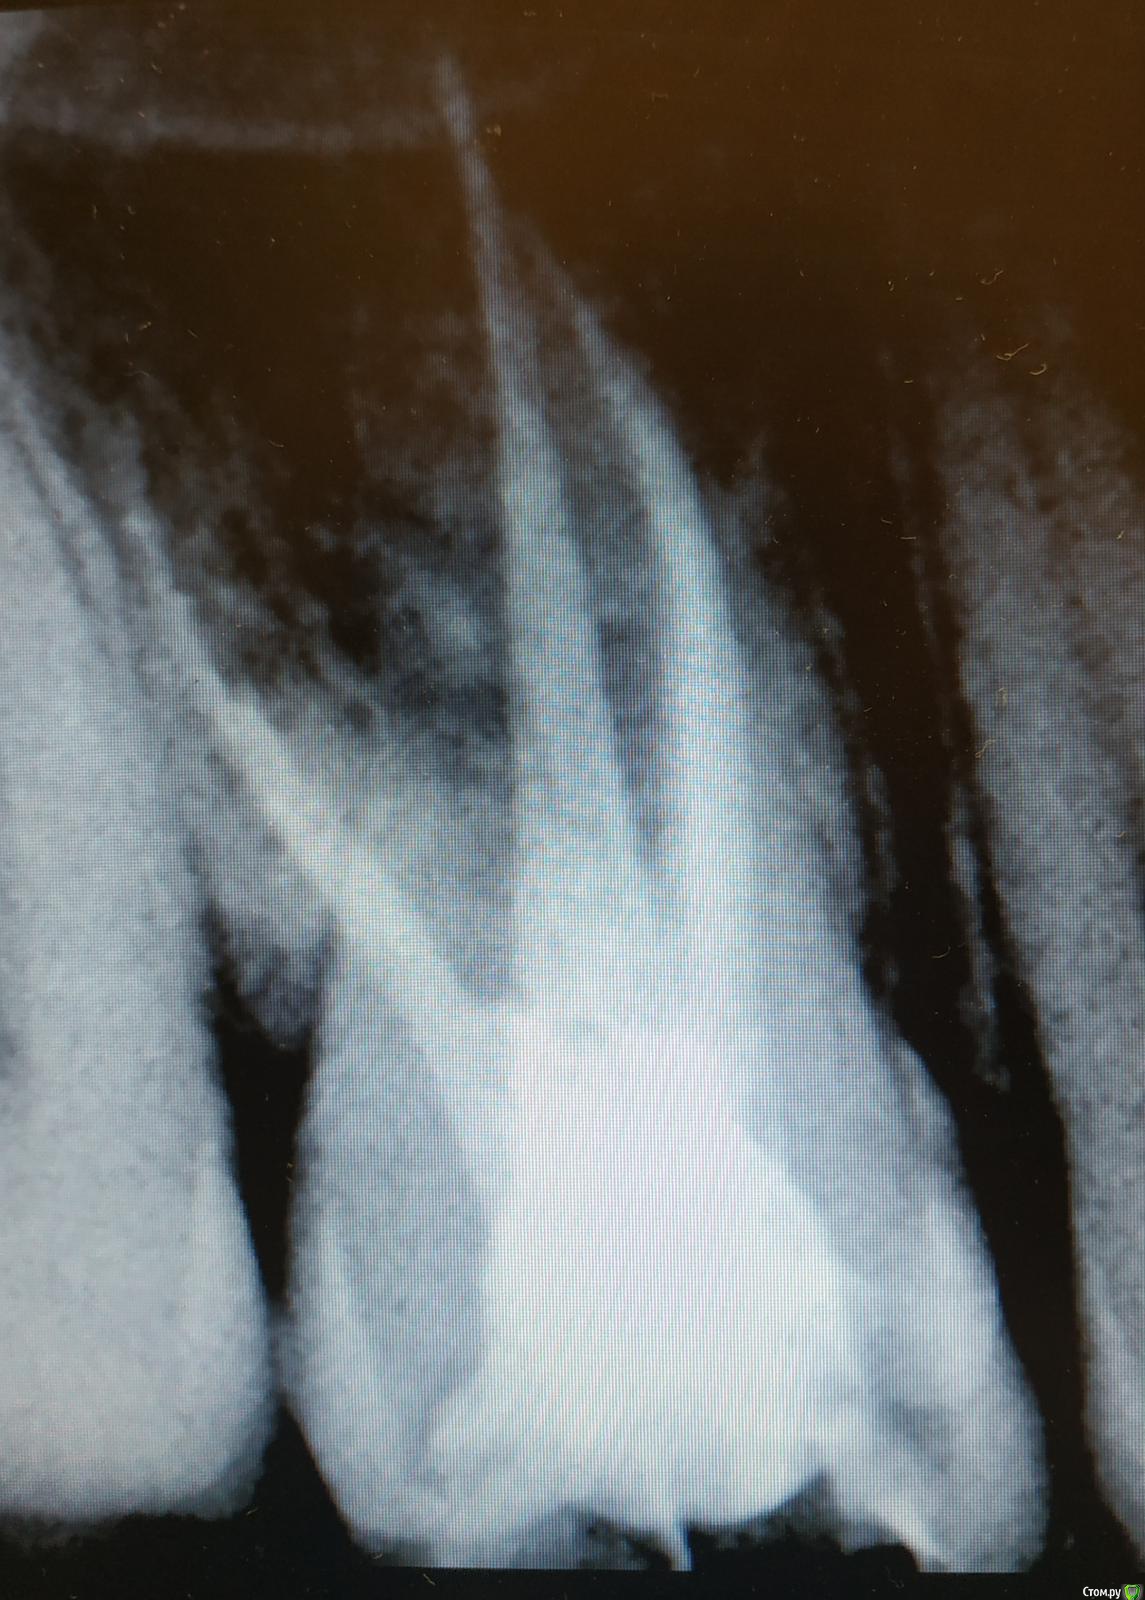

FVValerievna Опубликовано 14 сентября, 2019 Поделиться Опубликовано 14 сентября, 2019 Здравствуйте, подскажите пожалуйста, возможно ли, что пропущен канал? Ситуация такая: в полости рта четко видно 4 устья, на рентгене с инструментами тоже видно 4 канала, но на контрольном снимке не вижу 4й канал, хотя в полости рта запломбировано все 4 устья. Возможно ли такое наслоение? 1 Ссылка на комментарий

vse32 Опубликовано 14 сентября, 2019 Поделиться Опубликовано 14 сентября, 2019 Наслоение конечно возможно. Но на Вашем снимке после пломбировки видно, что каналов 4 штуки. Ссылка на комментарий